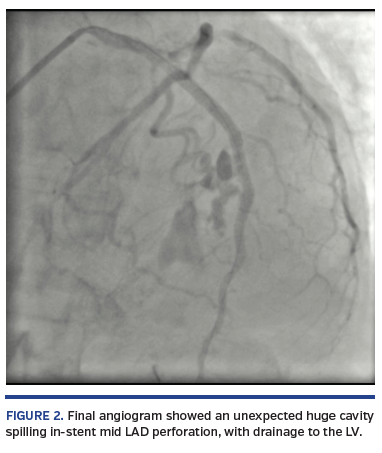

A short, 81-year-old woman presented with non-ST elevation acute myocardial infarction complicated with acute pulmonary edema. She was referred to urgent coronary angiography, performed via right distal transradial access, which is our default approach. The culprit left anterior descending (LAD) coronary artery was shown to have a long, tight, and calcified proximal-mid stenosis (Figure 1; Video 1), which was fixed by PCI with two drug-eluting stents (3 x 33 mm and 3.5 x 33 mm), requiring adequate pre- and postdilations with non-compliant balloons (2.5 x 20 mm and 3.5 x 20 mm, respectively). Surprisingly, the final angiogram showed an unexpected huge cavity spilling in-stent mid LAD perforation, with drainage to the left ventricle (Figure 2; Video 2). Promptly, the same postdilation NC 3.5 x 20 mm balloon was reinflated to 8 atm at the level of the CAP. After 10 minutes, there was some resolution. After a total 20 minutes of persistent balloon inflation without anticoagulation reversal, a final angiogram confirmed the CAP had been completely sealed without any residual contrast extravasation (Figure 3; Video 3). Transthoracic echocardiogram discharged pericardial effusion.

Type III cavity-spilling CAP (also called type IV CAP) is an unusual but dreaded complication, which can be conservatively managed with simple prolonged balloon inflation without compromising the final PCI result by anticoagulation reversal.